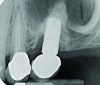

Peri-implant diseases present in two forms—peri-implant mucositis (Figure 1 and Figure 2) and peri-implantitis (Figure 3 and Figure 4). Both involve an inflammatory reaction in the tissues surrounding an implant—ie, bleeding on probing and/or suppuration; probing depths usually exceed 4 mm.1,3 However, when there is also bone loss present beyond the physiologic remodeling that may occur after implant placement, a diagnosis of peri-implantitis should be made, as this condition, when compared to mucositis, is far more serious and difficult to resolve.4

The authors believe, in accordance with the American Academy of Periodontology’s whitepaper,21 that clinicians should obtain radiographs that establish baseline bone levels both at the time of implant placement and immediately following final prosthesis insertion to facilitate comparison. They should also be taken at the first signs of disease that could signal bone loss, including change in tissue tone and color, bleeding, purulence, and increased or increasing probing depths—all of which should be evaluated at every visit.21